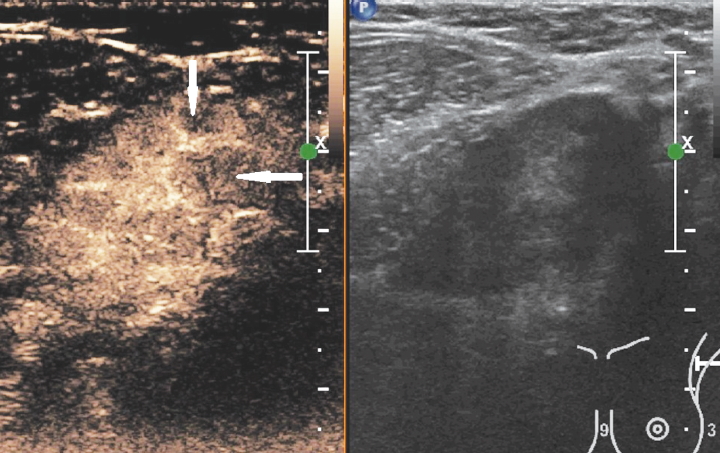

Наиболее удобным, доступным и хорошо изученным методом оценки статуса регионарных лимфатических узлов является УЗИ, при котором возможно оценить форму, контуры и структуру измененных лимфатических узлов. Для метастатических изменений характерна округлая и неправильная форма лимфатического узла (встречаются в 79% наблюдений); рис. 1. Также могут выявляться метастазы в лимфатических узлах с измененным корковым слоем, который проявляется его неравномерным утолщением или выбуханием контура на отдельном участке (рис. 2). Структура метастатически измененных лимфатических узлов многообразна и может быть гипоэхогенной, анэхогенной, гиперэхогенной, гетерогенной, с кальцинатами и даже с включениями жидкостного характера (рис. 3).

Рис. 2. Метастатические изменения подмышечного лимфатического узла в В-режиме: отмечается неравномерное утолщение коркового слоя с выбуханием контура на отдельном участке.

Fig. 2. B-mode ultrasound image of metastatic axillary lymph node: diffuse thickening of the cortex and cortical bulging of a separate part.

В последние годы широкое распространение получил метод ультразвуковой эластографии и эластометрии. Данная методика представляет собой способ дифференциации тканей по их жесткости путем механического воздействия на них и анализа деформаций, получаемых с помощью ультразвуковых диагностических сканеров [23]. Для оценки жесткости лимфатических узлов используется система качественной оценки результатов компрессионной эластографии лимфатических узлов, разработанная и M. Furukawa и соавт. в 2007 г. [24], согласно которой выделяют 4 степени жесткости узлов: 1-й тип (мягкие), 2-й (умеренно мягкие), 3-й (умеренно жесткие) и 4-й (жесткие). Для метастатических лимфатических узлов характерна жесткая и жестко-неоднородная структура, что соответствует 3 и 4-му типам эластографической картины по M. Furukawa, а для гиперплазированных лимфатических узлов – 1 и 2-й тип эластографической картины (рис. 5).

Рис. 5. Компрессионная эластография лимфатических узлов: а – лимфатический узел с метастатическими изменениями; отмечается неоднородная жесткая структура (3-й тип эластографической картины); б – гиперплазированный лимфатический узел (1-й тип эластографической картины).

Fig. 5. Strain elastography of lymph nodes: a – metastatic lymph node with heterogeneous hardness (elastographic pattern 3); b – hyperplastic lymph node (elastographic pattern 1).